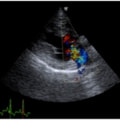

症例6:【ACVIM StageD ビーグル 10歳 去勢雄】

C:超音波 僧帽弁逆流のカラードップラー画像

左側胸壁心尖部領域を最強点とするLevine 5/6の収縮期性心雑音が聴取された。安静時にも咳が認められる。胸部レントゲン検査において重度の心拡大が及び肺水腫が認められた。超音波検査では、重度の僧帽弁閉鎖不全、三尖弁閉鎖不全が認められた。三尖弁逆流速度から肺高血圧症が示唆された。ACE阻害薬、ピモベンダン、硝酸イソソルビド徐放剤、ベラプロストナトリウム、利尿剤としてフロセミド及びスピロノラクトンを用いて治療を行っている。